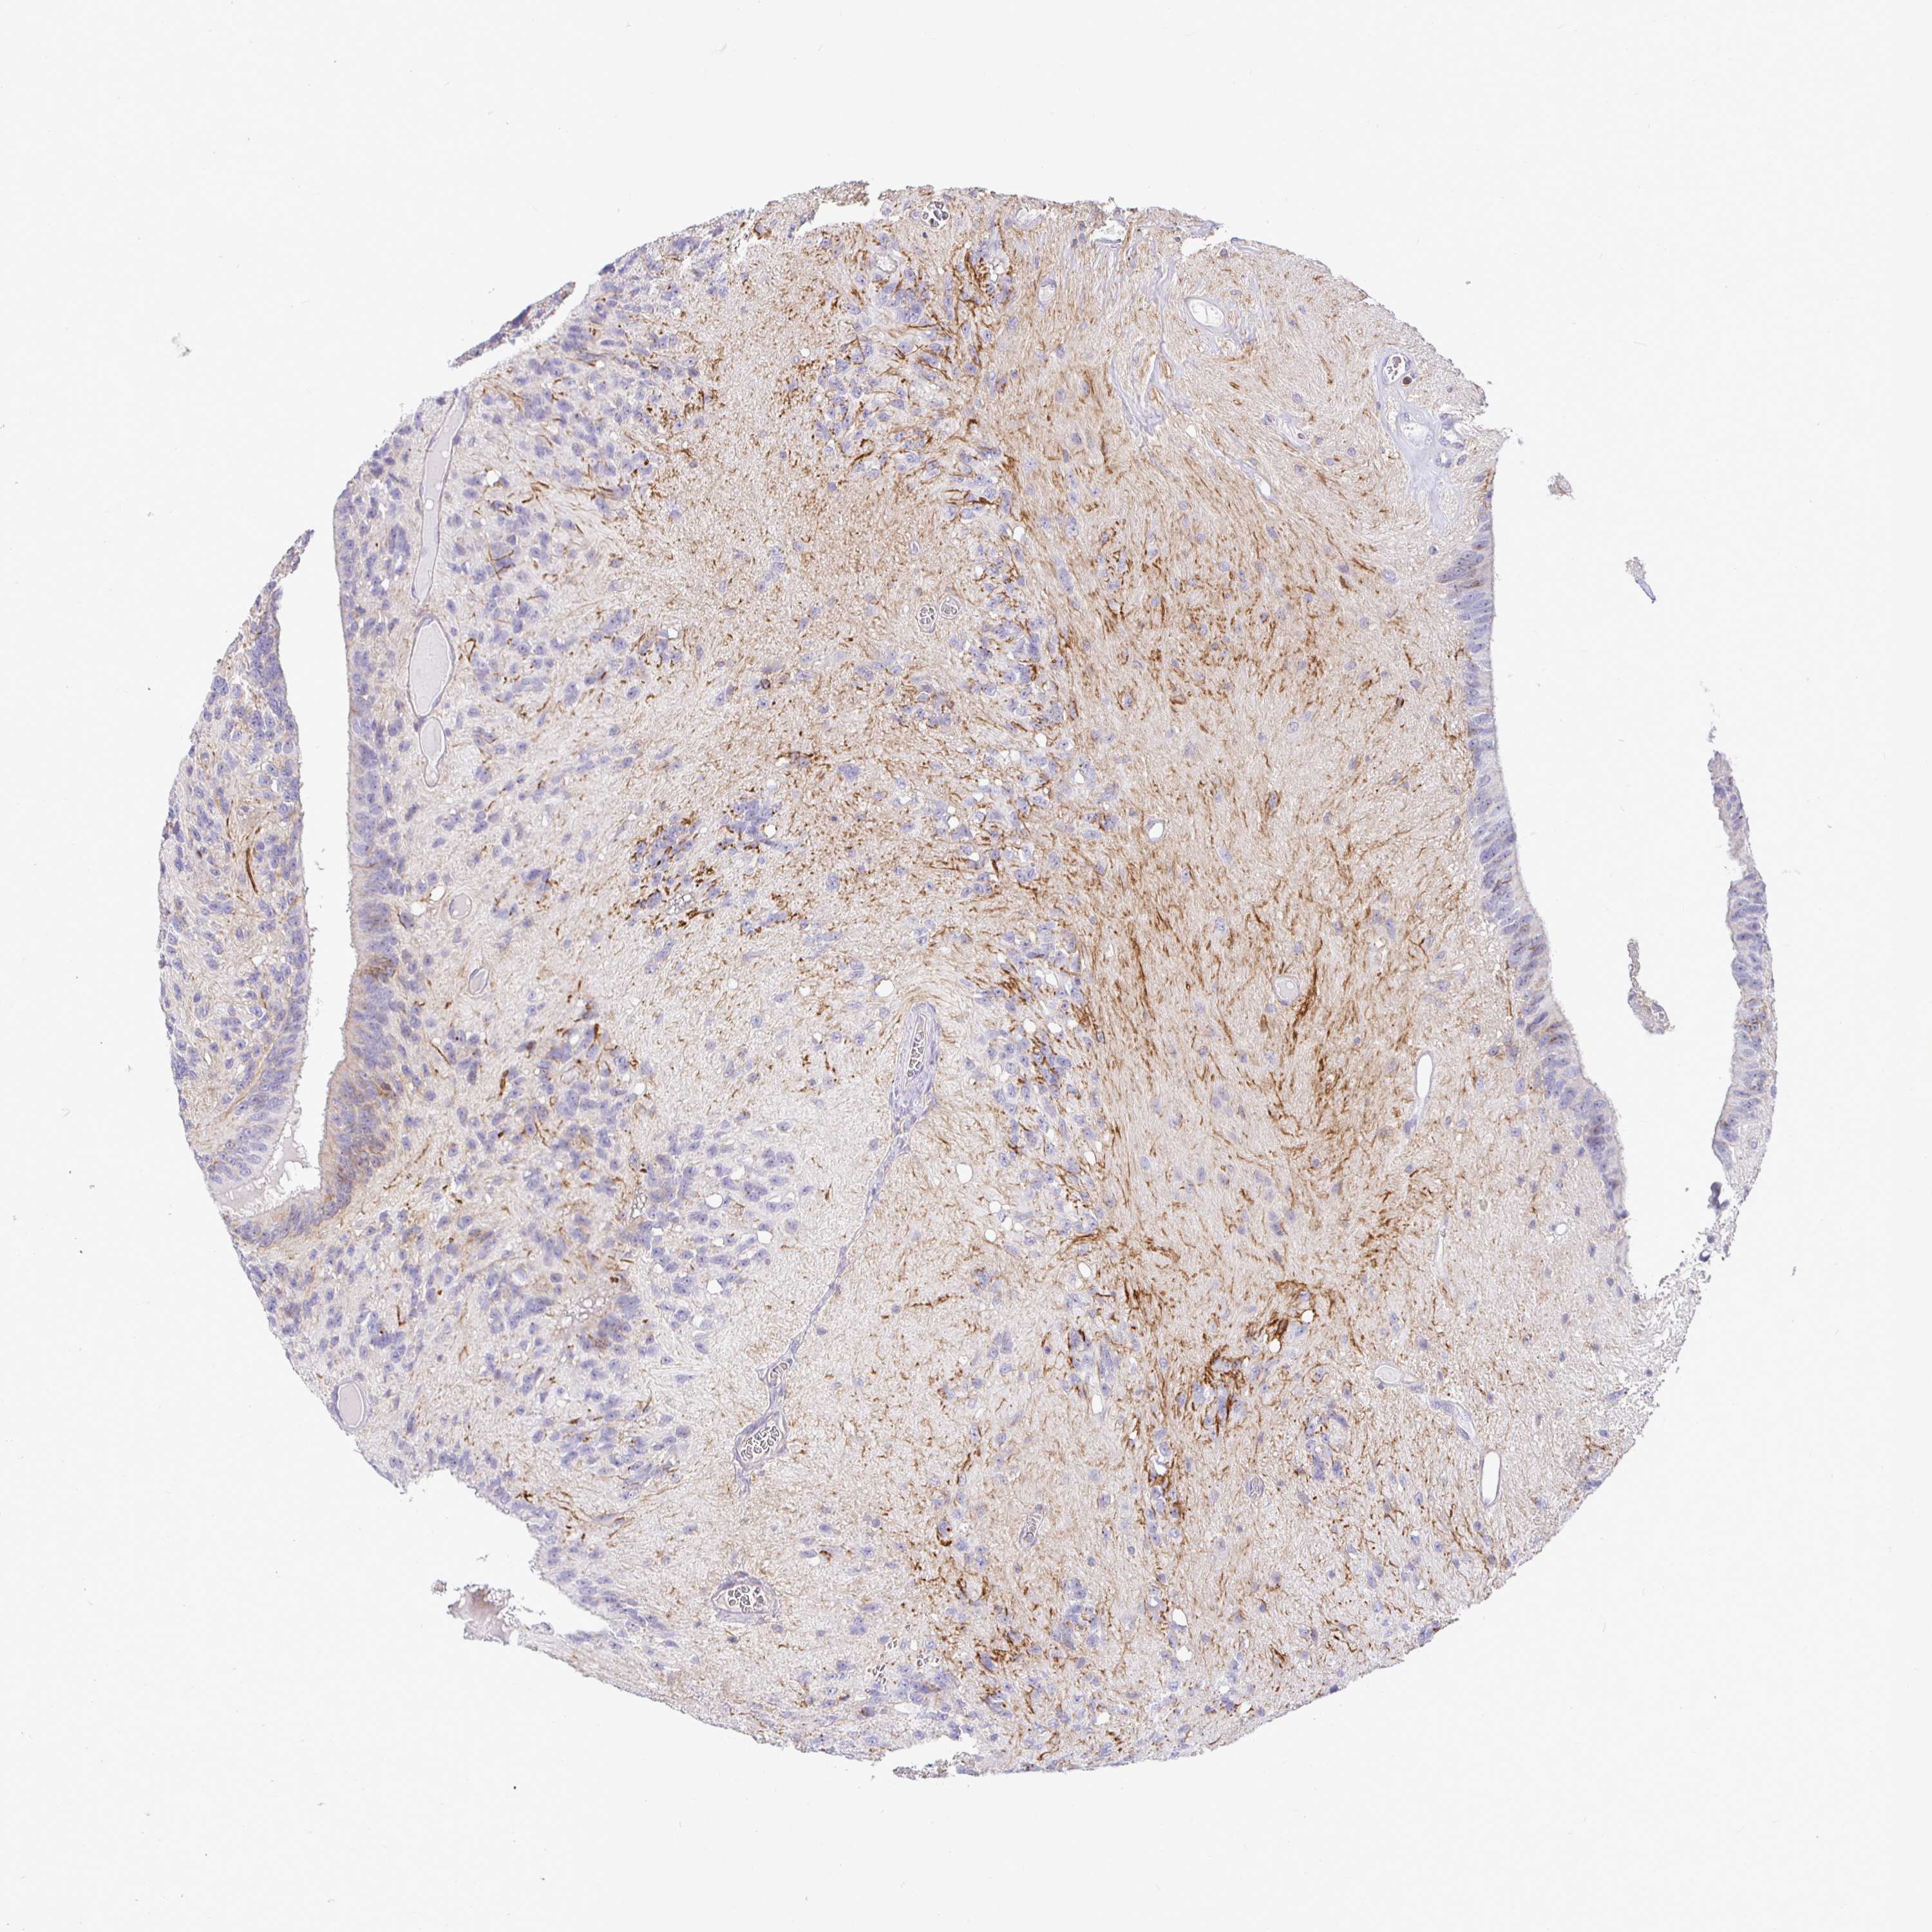

GLIOMA - Protein expressioni

A mouse-over function shows sample information and annotation data. Click on an image to view it in a full screen mode. Samples can be filtered based on level of antibody staining by selecting one or several of the following categories: high, medium, low and not detected. The assay and annotation is described here.

Note that samples used for immunohistochemistry by the Human Protein Atlas do not correspond to samples in the TCGA dataset.

Antibody stainingi

Antibody staining in the annotated cell types in the current human tissue is reported as not detected, low, medium, or high, based on conventional immunohistochemistry profiling in selected tissues. This score is based on the combination of the staining intensity and fraction of stained cells.

Each image is clickable and will lead to virtual microscopy that enables deeper exploration of all samples and also displays staining intensity scores, fraction scores and subcellular localization as well as patient and tissue information for each sample.

Antibody HPA054437

Antibody HPA058511

Antibody CAB002776

Antibody CAB015122

Glioma, malignant, Low grade

Glioma, malignant, High grade

Glioma, malignant, NOS